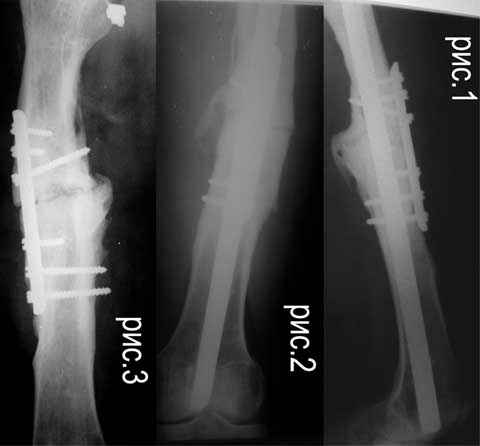

Re: ложный сустав средней трети бедра

Alexander Chelnokov 16 Декабрь 2006, 09:17

Если нет инфеекции и укорочения, то закрытое штифтование с блокированием должно решить проблему. Хотя, видимо, стержень можно ввести как есть, пластину лучше убрать. Инфекция или укорочение при той же окончательной фиксация потребуют дополнительных мер.

Отправитель: Дрягин 16 Декабрь 2006, 12:39

Полностью согласен с Александром.Единственно Вы не акцентировали с рассверливанием или без.Я бы с рассверливанием.

Судя по картинке - достаточно лишь стабилизировать. IMHO здесь рассверливание большого самостоятельного зачения не имеет. Канал должен быть чуть шире выбранного стержня. Если для этого придется рассверлить - то и ладно, если и так широкий - тоже не беда. Стержень взять диаметром 12-13 мм. Если укорочения нет - еще компрессию дать.

Царицанский С 17 Декабрь 2006, 00:36

Спасибо за отклики. Судя по количеству-мнение однозначное. Можно ли уточнить некоторые детали: 1.IMHO без обработки концов отломков? 2.без костной пластики? 3.блокирование динамическое?4.при весе 60 кг достаточно ли по 1 винту 4,8 мм? 5.предлагают штифт от SANATMETAL (FWDA)- подойдет ли 6.нет ли отечественного (более дешевого) варианта? (упоминаемый на форуме Metadiafix в прайсах ФГУП ЦИТО не нашел)

AC>По длине - уже "семь раз отмерили"? С длиной ве-таки как дело обстоит? И виден небольшой варус, надо бы и его устранить.

укорочение 15мм, клинически варуса нет. в приложении снимок на 2 пленках с центр на суставах, с приклеенной на уровне кости стержнем L-300mm,d-5mm.